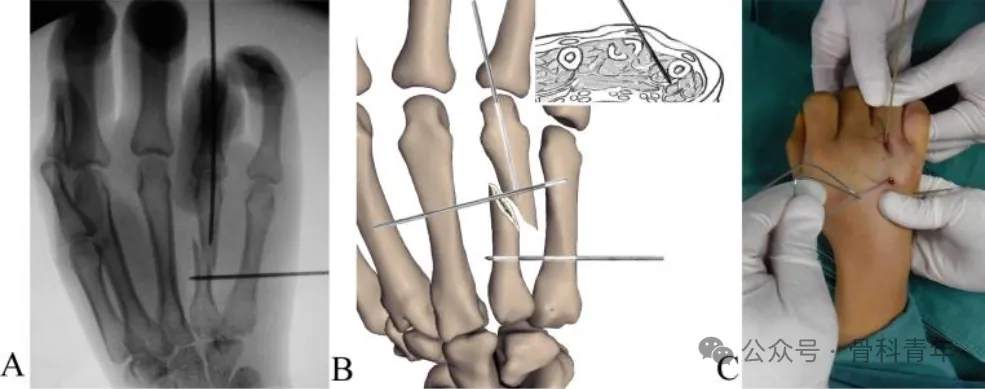

步骤1:常规消毒铺巾,尺神经阻滞麻醉。掌骨骨折通常远端移位,近端因腕掌关节及临近掌骨的存在,位置相对固定。先将一枚1.5mm克氏针经第5掌骨穿入第4掌骨骨折近端,将骨折近端固定。

步骤2:掌指关节屈曲90°,经掌骨远端关节面置入一枚1.5mm克氏针,穿入远端骨块髓内。后牵引环指、挤压骨折断端闭合复位,如复位困难,可采用克氏针经皮撬拨或将克氏针折弯后辅助复位(如下图)。

步骤3:复位后,将远端髓内克氏针直接穿入近端骨块髓腔,临时维持复位。在位置满意后,经第5掌骨置入2枚克氏针至远端骨块,再置入一枚固定近端。在远近端各固定2枚后,去除髓内固定克氏针。固定后克氏针留置皮外,可回归工作。